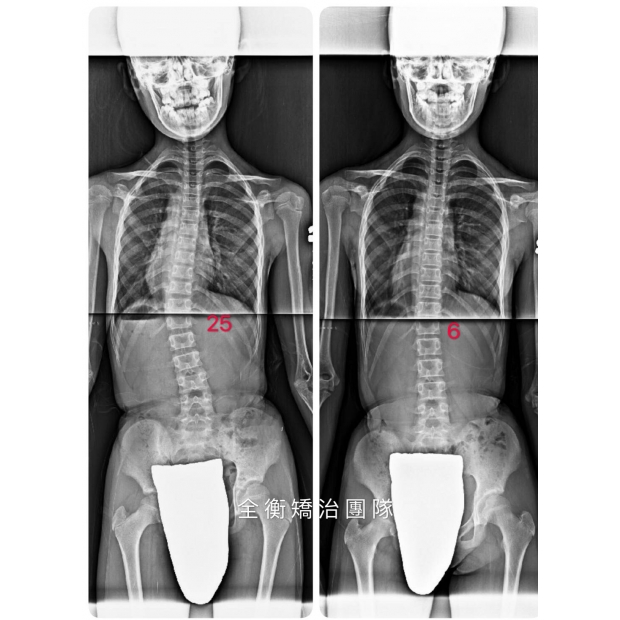

11歲24度側彎女孩,把握脊椎側彎黃金矯正期,收穫驚喜連連11歲24度側彎女孩,把握脊椎側彎黃金矯正期,收穫驚喜連連

11歲24度側彎女孩

治療一年後脊椎幾乎變直

24°→8°→2° -